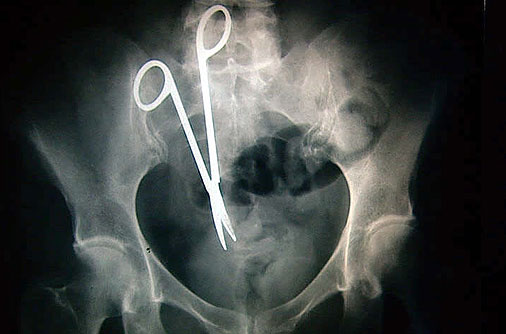

8②のハサミって医療ミスかよ。

リアルに本間先生みたいなミスする先生いるんだ…

ガーゼの体内置き忘れは年に一度か二度くらいニュースで見るから、こういうのって発覚してないもの含めたら結構多いんじゃない?

にしたって刃物は怖いよね